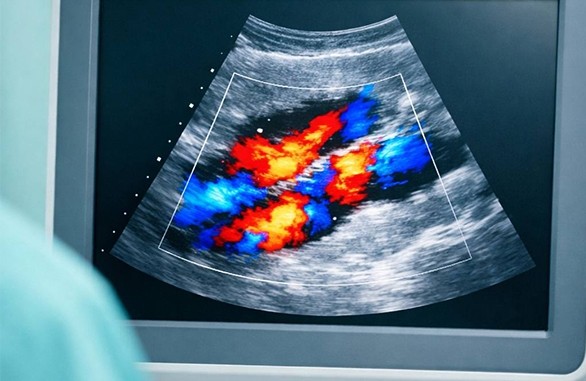

Возможности допплера в УЗИ

Иногда во время УЗИ врач включает допплер - на экране появляются цвета. Это не визуальный эффект - а диагностическая информация

Что такое допплер при УЗИ?

Это режим исследования, позволяющий оценить кровоток:

• есть ли он

• направление движения крови

• скорость потока

Ультразвуковая волна отражается от движущихся эритроцитов и меняет частоту сигнала.

Почему кровь отображается цветом?

• Красный - движение крови к датчику

• Синий - движение от датчика

• Ярче оттенки - выше скорость потока

Это помогает врачу оценить кровоснабжение органов и тканей.